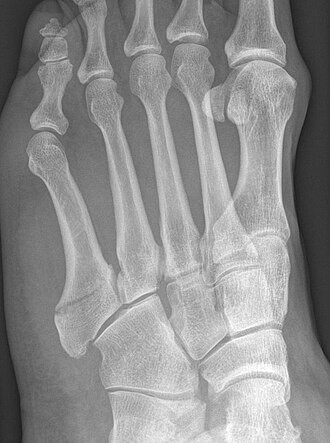

La fractura del 5é metatarsià es diu “fractura de Jones”, després que ho publiqués als Annals of Surgery el 1902, amb una sèrie de malalts amb aquesta fractura (Fig.2).